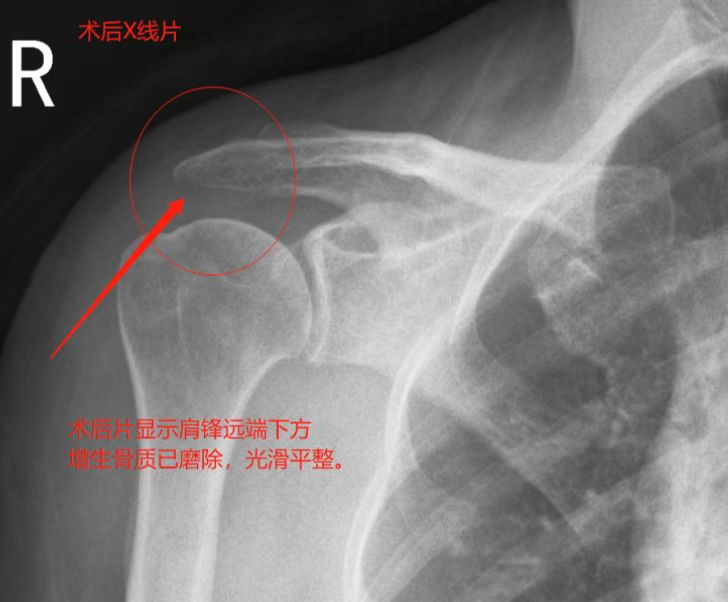

▲术后复查DR肩峰下撞击已解除

术后患者右肩关节功能基本达正常范围,疼痛感已基本缓解,术后4天患者满意出院。